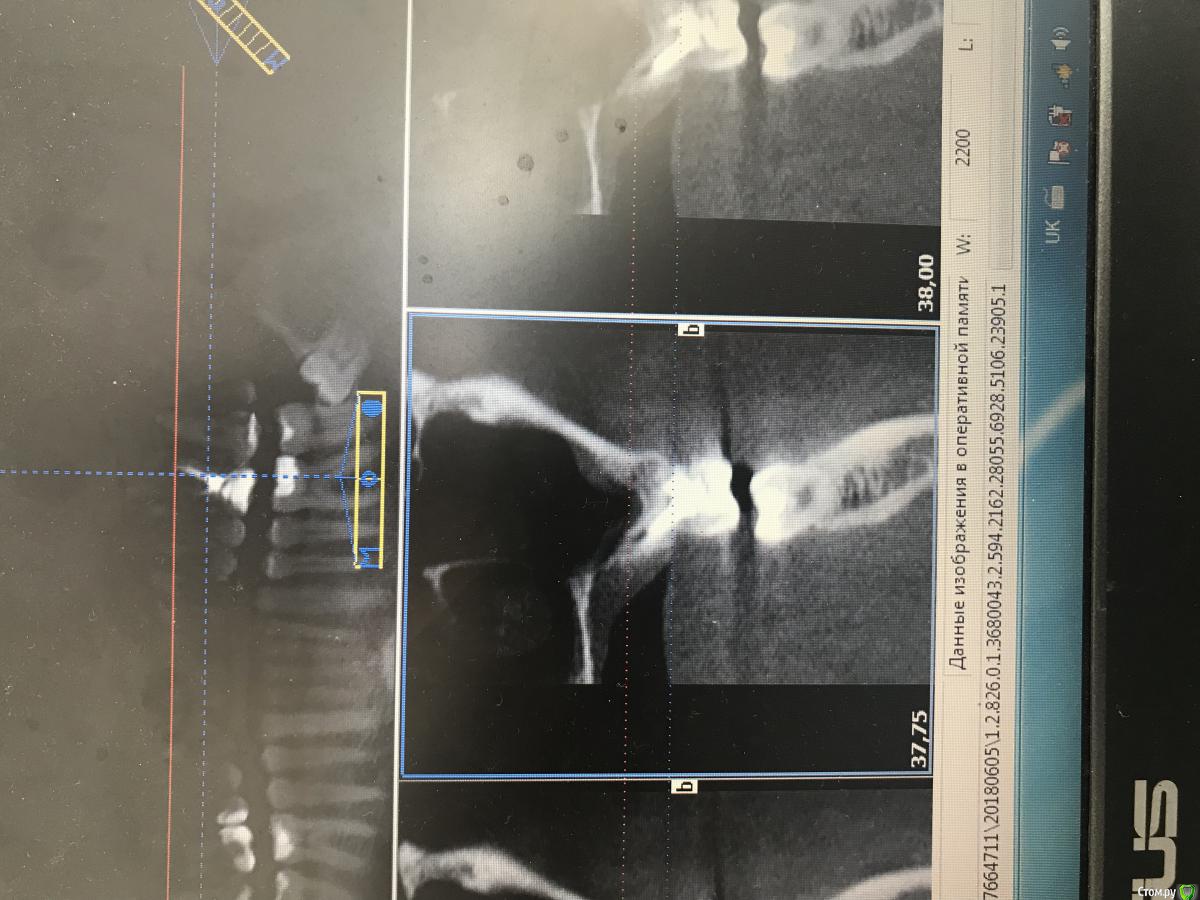

dr.Dre Опубликовано 6 июня, 2018 Поделиться Опубликовано 6 июня, 2018 (изменено) Добрый день ,коллеги такой клинический случай ,пациента нос заложен постоянно лор напривил сказал гайморит от зубов ,я думаю , что причина в 26 ,что скажите? Изменено 6 июня, 2018 пользователем dr.Dre Ссылка на комментарий

Дмитрий Л. Опубликовано 6 июня, 2018 Поделиться Опубликовано 6 июня, 2018 извините пожалуйста загрузил с телефона, у меня есть кт как можно загрузить на форум?Загрузить на файлообменник или облако (гугл диск, к примеру) и затем ссылку сюда. Я бы обратил внимание на 16. Но данных мало вы предоставили... гайморит... какой, 1-, 2-сторонний? Срезы непонятные Заложенность носа это ещё не гайморит. Жалобы на "зубы"? Перкуссия и т.д. Ссылка на комментарий

dr.Dre Опубликовано 6 июня, 2018 Автор Поделиться Опубликовано 6 июня, 2018 Загрузить на файлообменник или облако (гугл диск, к примеру) и затем ссылку сюда. Я бы обратил внимание на 16. Но данных мало вы предоставили... гайморит... какой, 1-, 2-сторонний? Срезы непонятные Заложенность носа это ещё не гайморит. Жалобы на "зубы"? Перкуссия и т.д.https://fex.net/714551533241 Ссылка на комментарий